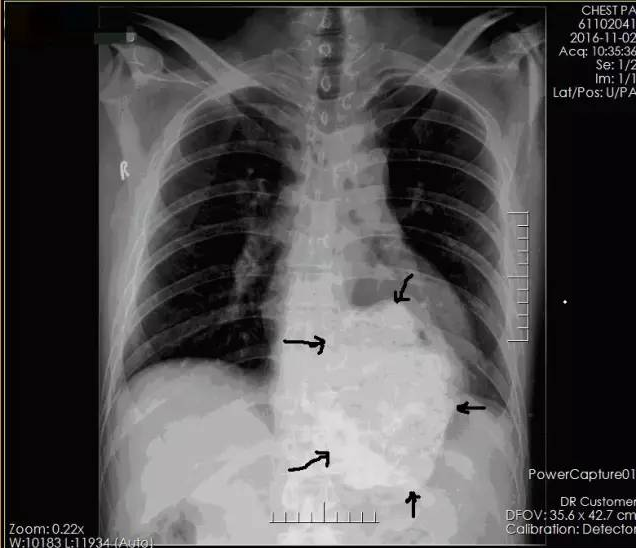

患者术前X线片

术前讨论